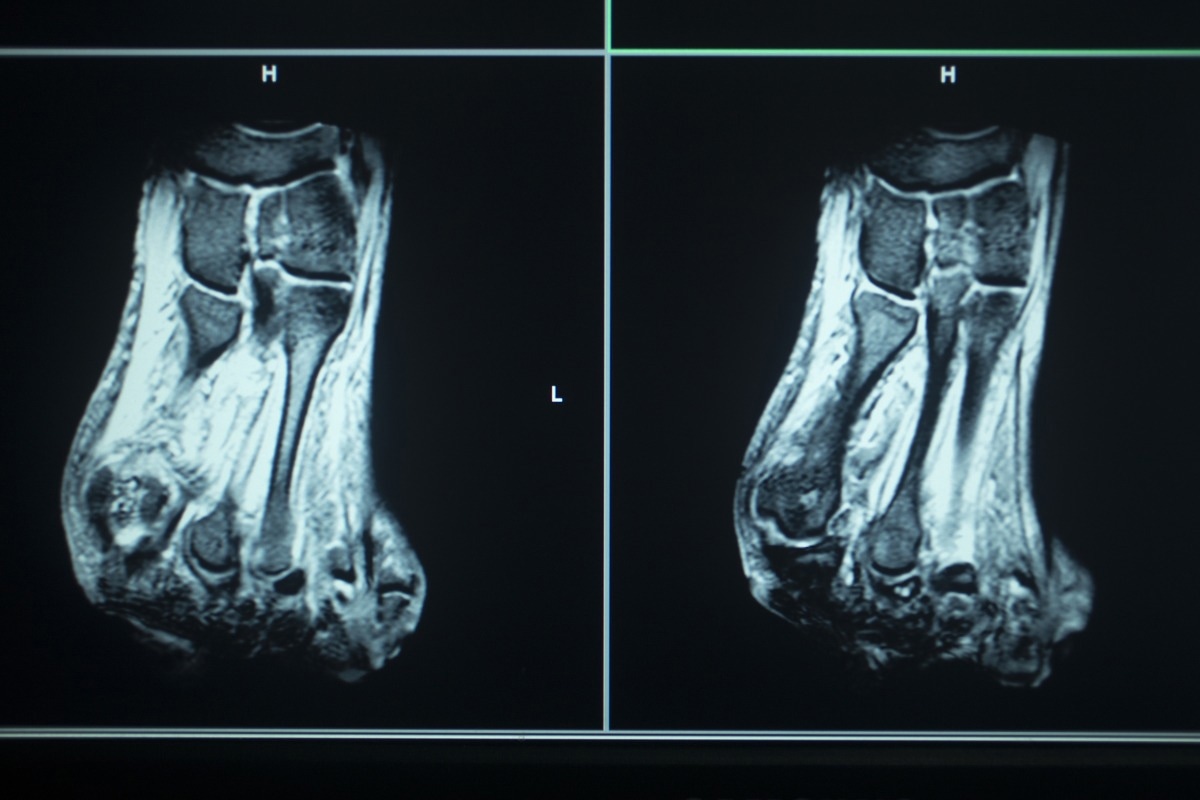

Medical imaging is used routinely to investigate biological mechanisms, monitor disease progression, and in the context of diagnosis. Several imaging techniques are being developed to enhance the resolution of images across magnetic resonance imaging (MRI), computed tomography (CT), position emission tomography (PET), single-photon emission computed tomography (SPECT), ultrasound imaging, photoacoustic (PA)imaging, and optical fluorescence imaging.

MRI is the most favored imaging approach, and ineffective tool for cancer diagnosis owing to its high spatial resolution, high contrast imaging of soft tissues, and results in less exposure to radiation. Nuclear magnetic resonance and MRI function use the same concept. However, MRI uses a strong magnetic field applied to the whole body.